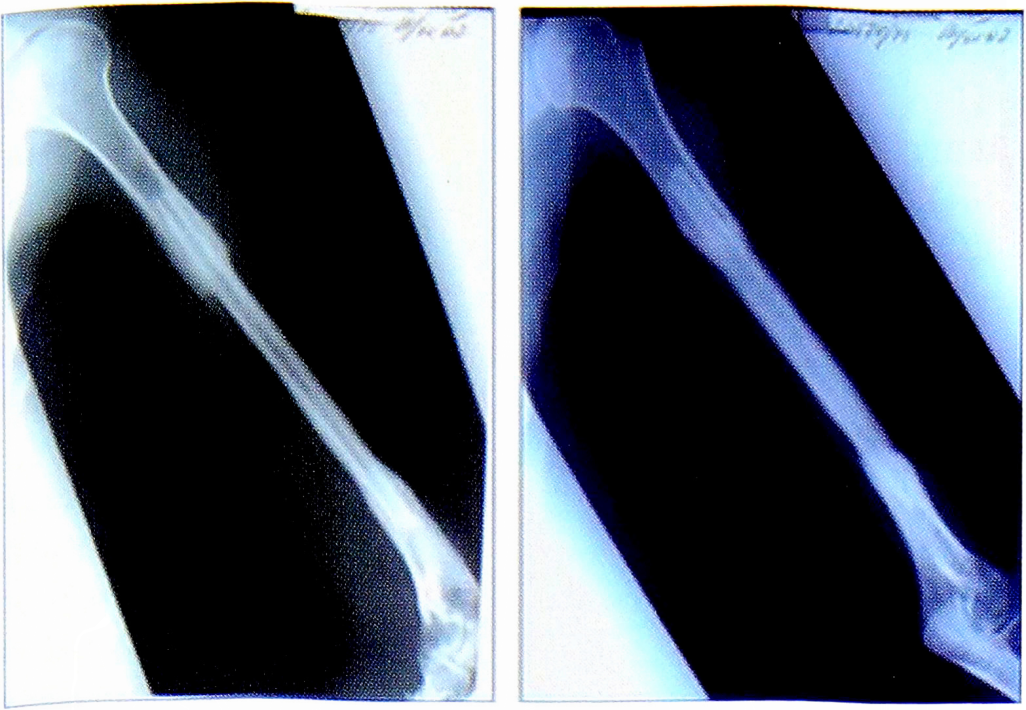

Рис. 10. Рентгенограмма пациентки Н. до операции.

Fig. 10. Radiograph of patient N. before surgery.

Рис. 12. Рентгенограммы пациентки H. после операции.

Fig. 12. Radiographs of patient N. after surgery.

Рис. 13. Рентгенограммы пациентки H. через 8 мес после операции.

Fig. 13. Radiographs of patient N. 8 months after surgery.